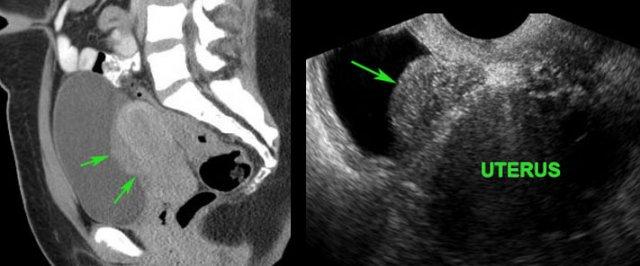

Lạc nội mạc tử cung tại bàng quang

Phát hiện tình cờ “polyp bàng quang” (mũi tên) trên CT ở bệnh nhân nữ trẻ.

Xác nhận cấu trúc dạng polyp dẹt (mũi tên) bằng siêu âm bụng.

Nội soi bàng quang hoàn toàn bình thường, cho thấy khối được phủ bởi niêm mạc bàng quang bình thường.

TVUS chứng minh khối thực chất là một ổ lạc nội mạc tử cung và cho thấy bờ tăng âm (*) của tử cung bị mờ, gợi ý xâm lấn khu trú.

TVUS cũng phát hiện DIE trong túi cùng Douglas (không hiển thị ở đây).

Bệnh nhân nữ 45 tuổi với tiền sử đau khi tiểu tiện kéo dài. Nội soi bàng quang âm tính.

CT cho thấy một khối dạng mảng bám, bờ không đều (mũi tên).

TVUS xác nhận một ổ lạc nội mạc tử cung lớn (mũi tên) trong khoang trước bàng quang (khoang Retzius). Lưu ý bờ không rõ với tử cung.